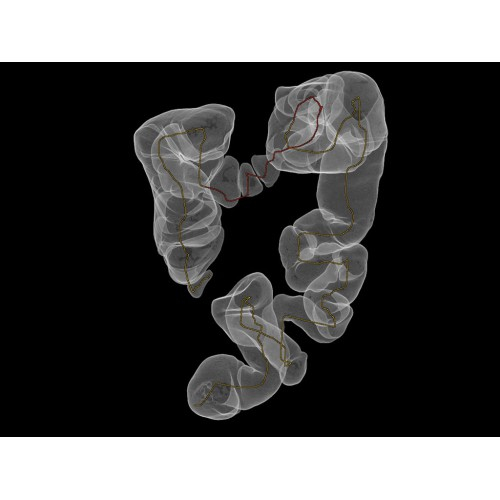

Позволяет проводить комплексные исследования всех анатомических зон, включая нейровизуализацию, ангиографию, исследования органов грудной и брюшной полости. Особенно эффективен для раннего выявления онкологических заболеваний.

Специализированные исследования